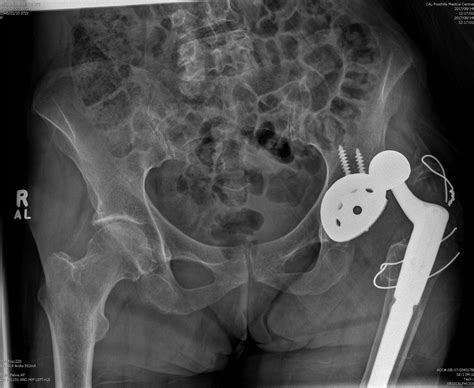

Total Hip Arthroplasty (Hip Replacement)

If the hip joint has already developed advanced osteoarthritis due to chronic dysplasia, the cartilage is often too damaged for preservation. In these instances, a total hip replacement is the most reliable option. The damaged ball and socket are replaced with artificial components, effectively resolving the pain associated with bone-on-bone friction.